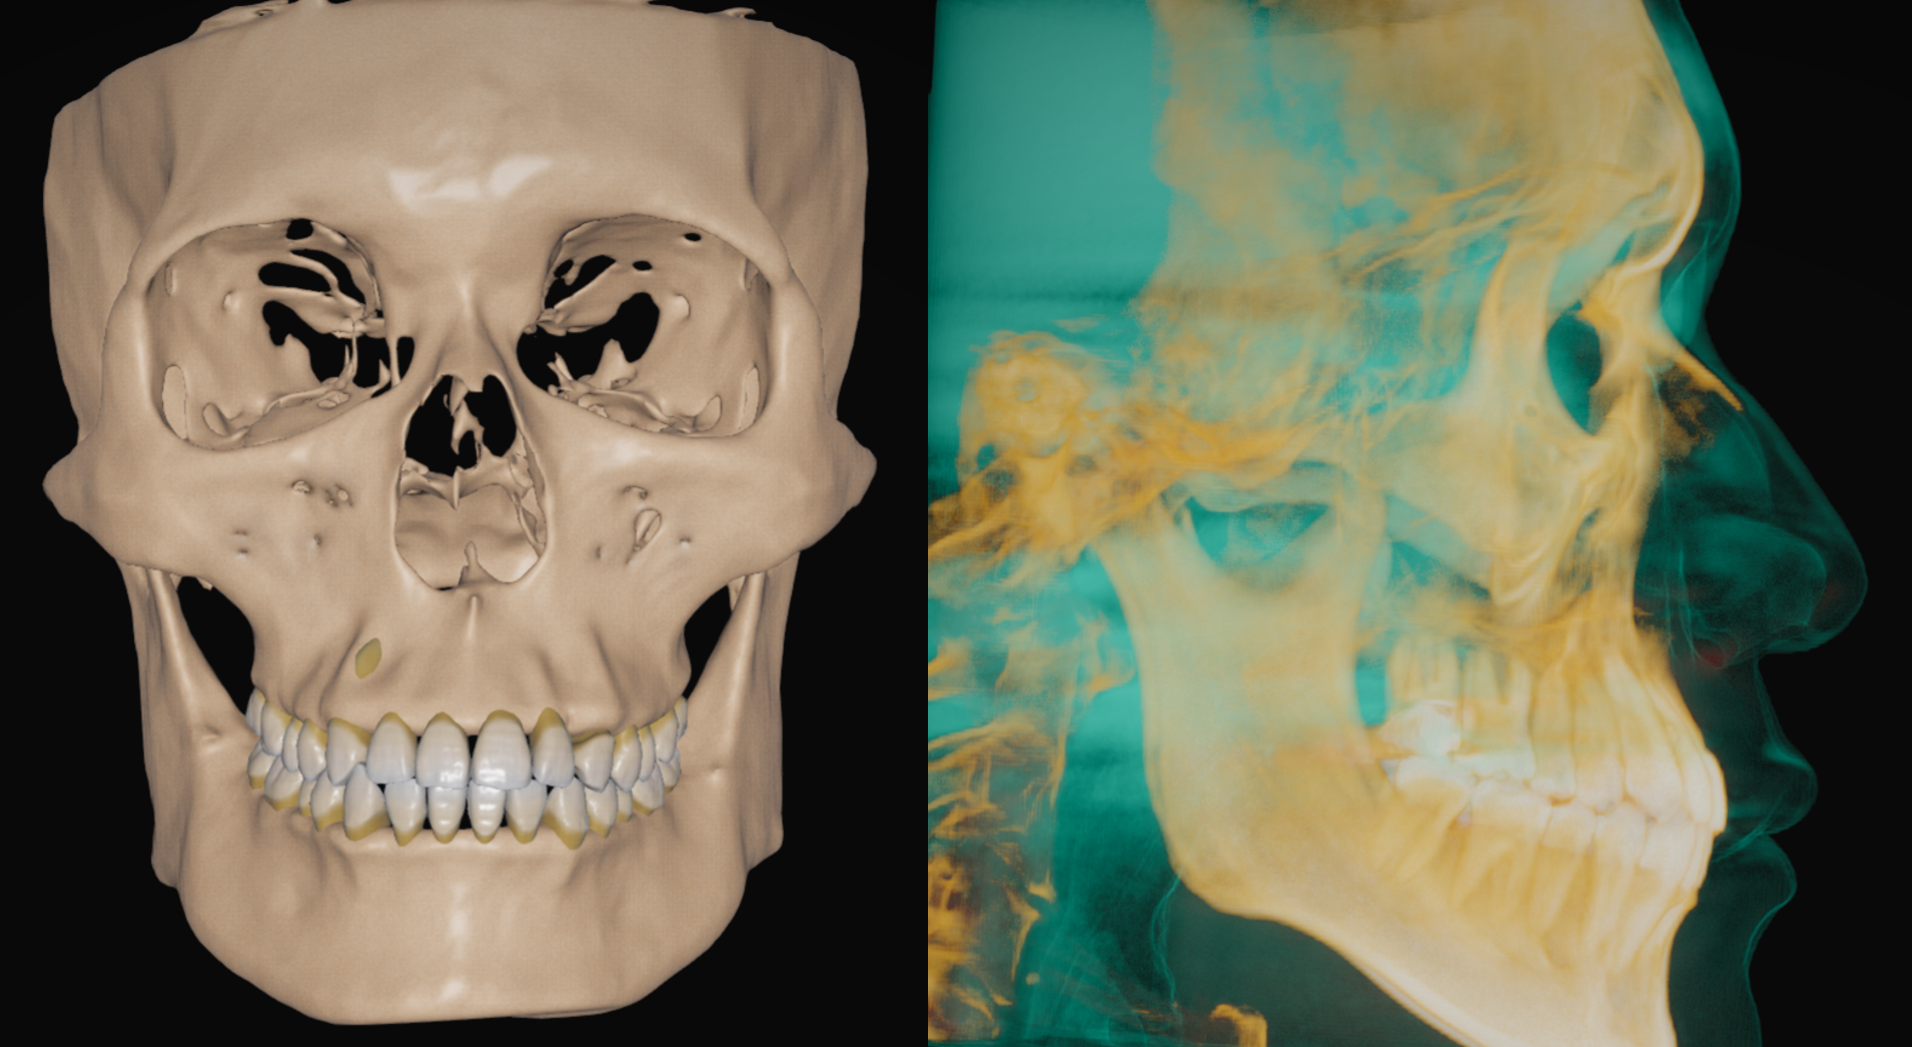

①CT

歯を動かす際には、歯を支える歯槽骨の状況を見る必要があります。

例えば、歯周病が進行している部位は歯槽骨の厚みや高さが足りていないことがあります。骨量が少ない方へ歯を動かすと歯茎の位置が下がってしまい、ブラックトライアングルという歯と歯の間に三角形の隙間ができてしまうことがあります。

また、上顎前歯部の後方にある切歯管という組織の位置関係も重要であり、「とにかく前歯を下げたい!」ということが主訴であったとしても、切歯管と前歯の位置が近いと前歯を引っ込める際に歯根が切歯管にぶつかり吸収されてしまうことがあります。その際は前歯を下げる量を妥協せざるを得ない場合もございます。

子供の方でも大人の方でも、歯が骨の中に埋まっている埋伏歯の位置関係を見ることもできます。

歯と骨の総合的な情報を得るためにCTは必須になります。

②フェイススキャン

上記のCTデータを組み合わせることで、皮膚と骨の位置関係をより詳細に知ることができます。

また、治療が進んできた時に再度スキャンすることで、治療前後の口元や顔貌の変化を比較することができます。

デジタル上で歯型を取ります。スキャンデータをCTと合わせることで、口腔内の状態を正確に再現できます。